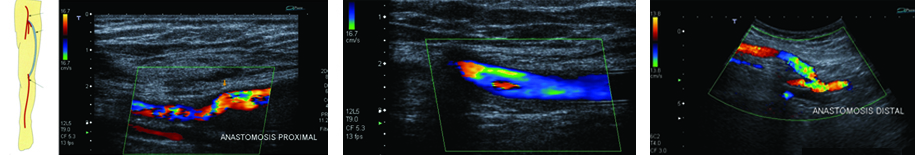

IMÁGENES POSTQUIRÚRGICAS

Realizado el diagnóstico de la arteriopatía, nivel de estenosis y grado de colateralización, el cirujano planteará la cirugía. Es importante para el médico radiólogo saber el tipo de cirugía realizada y el tiempo de evolución de la misma para una correcta interpretación de las imágenes.

Metodología de examen

De no contar con información sobre el tipo de cirugía realizada, el médico radiólogo llevará a cabo una anamnesis al paciente sobre el tema y la sintomatología actual; asimismo lo examinará en búsqueda de cicatrices que le permitan reconocer la técnica empleada. Luego procederá a evaluar el tipo de injerto y la topografía del bypass, realizará la medición de las velocidades de flujo en las anastomosis y en el injerto, y procederá a medir el índice tobillo-braquial. Identificará el tipo de bypass femoral. Durante el examen se evaluará la velocidad de pico sistólico en el sector de las anastomosis y en el injerto. En el período postquirúrgico el flujo típico es de hiperemia, con diástoles prominentes. Al cabo de dos meses se establece un patrón trifásico típico. La velocidad en el bypass debe ser superior a 40 cm/seg (Fig. 21).